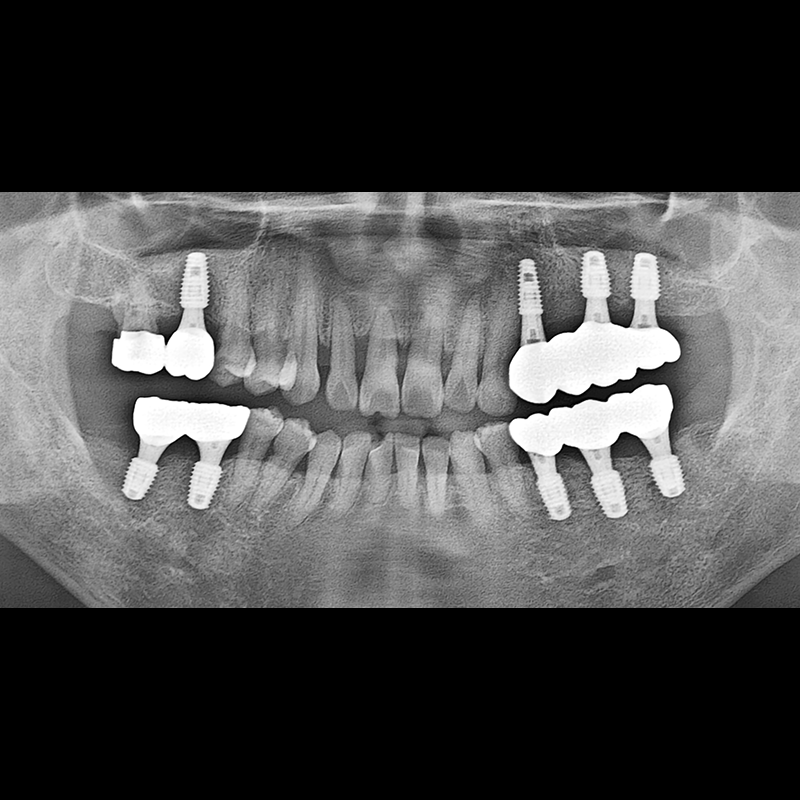

IMPLANT

BEFORE AFTER

种植牙前后的照片 2025.05.30

在缺失的牙齿部分和难以挽救的牙齿位置植入了种植牙。